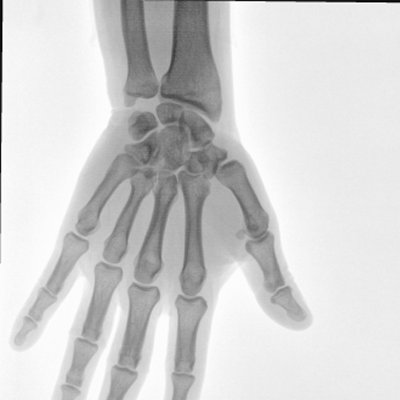

大尺寸動態(tài)平板探測器,高DQE、低噪聲、圖像清晰。采用多分辨率圖像增強(qiáng)處理技術(shù),不同部位不同圖像處理算法,滿足客戶多樣化的需求。

圖形化操控界面設(shè)計:設(shè)有多種人體特征攝影參數(shù),操作簡便。雙向紅光十字定位系統(tǒng):實現(xiàn)無射線下的高效定位。信息共享:遵循DICOM3.0格式接口,可無縫對接云PACS系統(tǒng)。